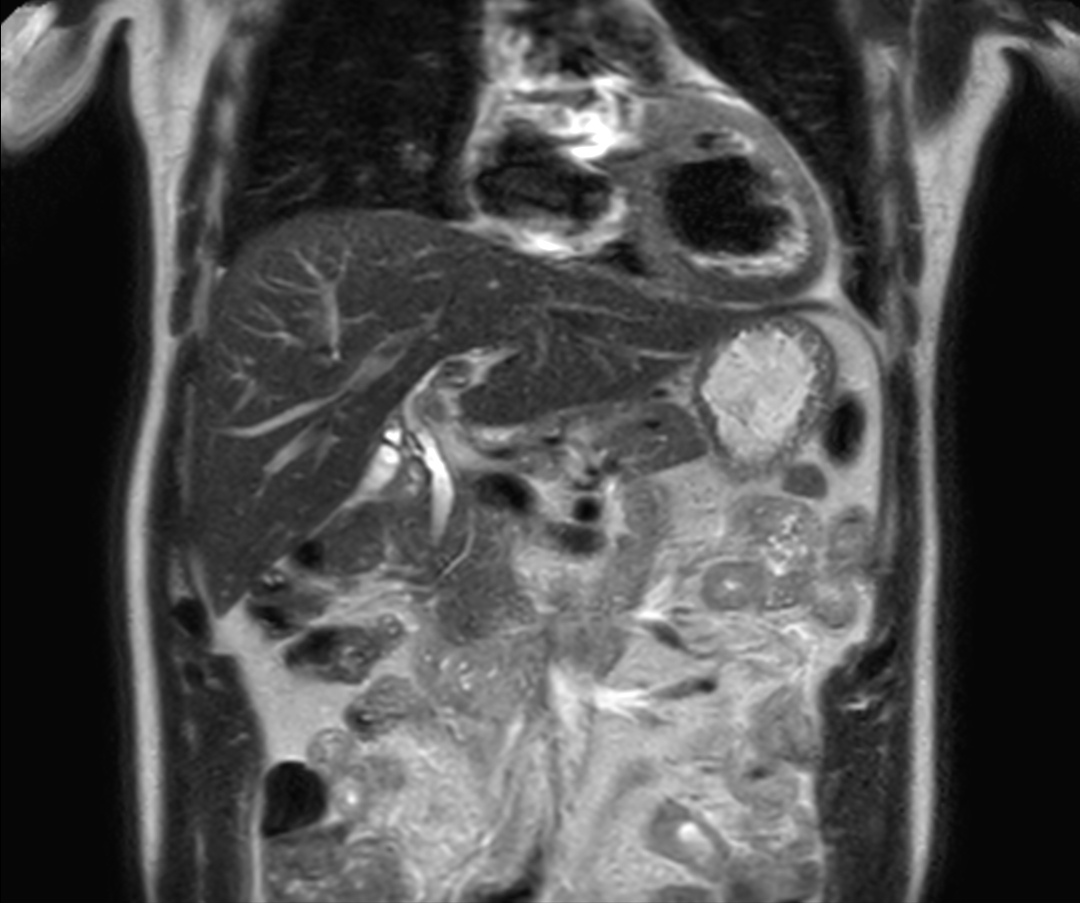

Helium-free MR operations:

Liver on BlueSeal magnet

Spital Uster, Switzerland

• Coil

• Clinical Application